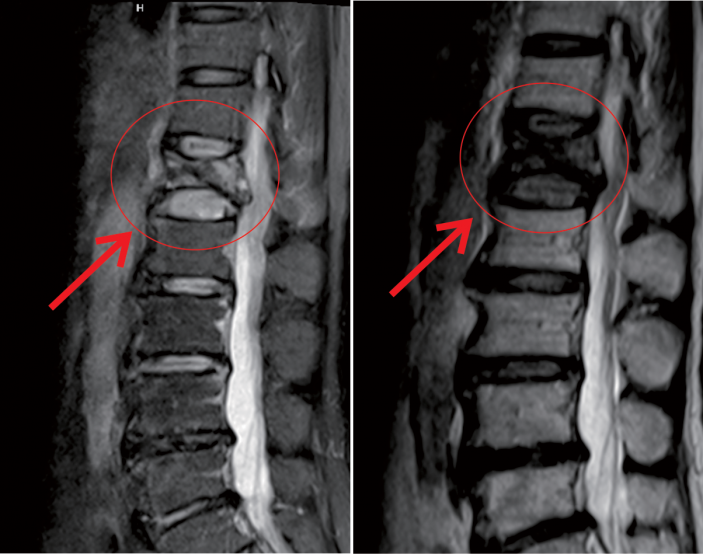

△術前MR顯示,第一腰椎壓縮性骨折

△術後,病變的椎體迅速恢複了功能

在我院先進的術中三維CT引導下,杜教授确定L1雙側椎弓根進針點,娴熟地将穿刺針穿入L1椎體,經穿刺針建立通道将約11ml骨水泥注入坍塌的椎體中。術中監視,注入的骨水泥逐漸支撐起原本壓縮空洞的椎體。骨水泥凝固後,病變的椎體迅速恢複了承重能力。手術持續約40分鍾,開展非常成功,術後老人的疼痛馬上消失,翻身也無疼痛,第二天就能使用助步器下地行走。